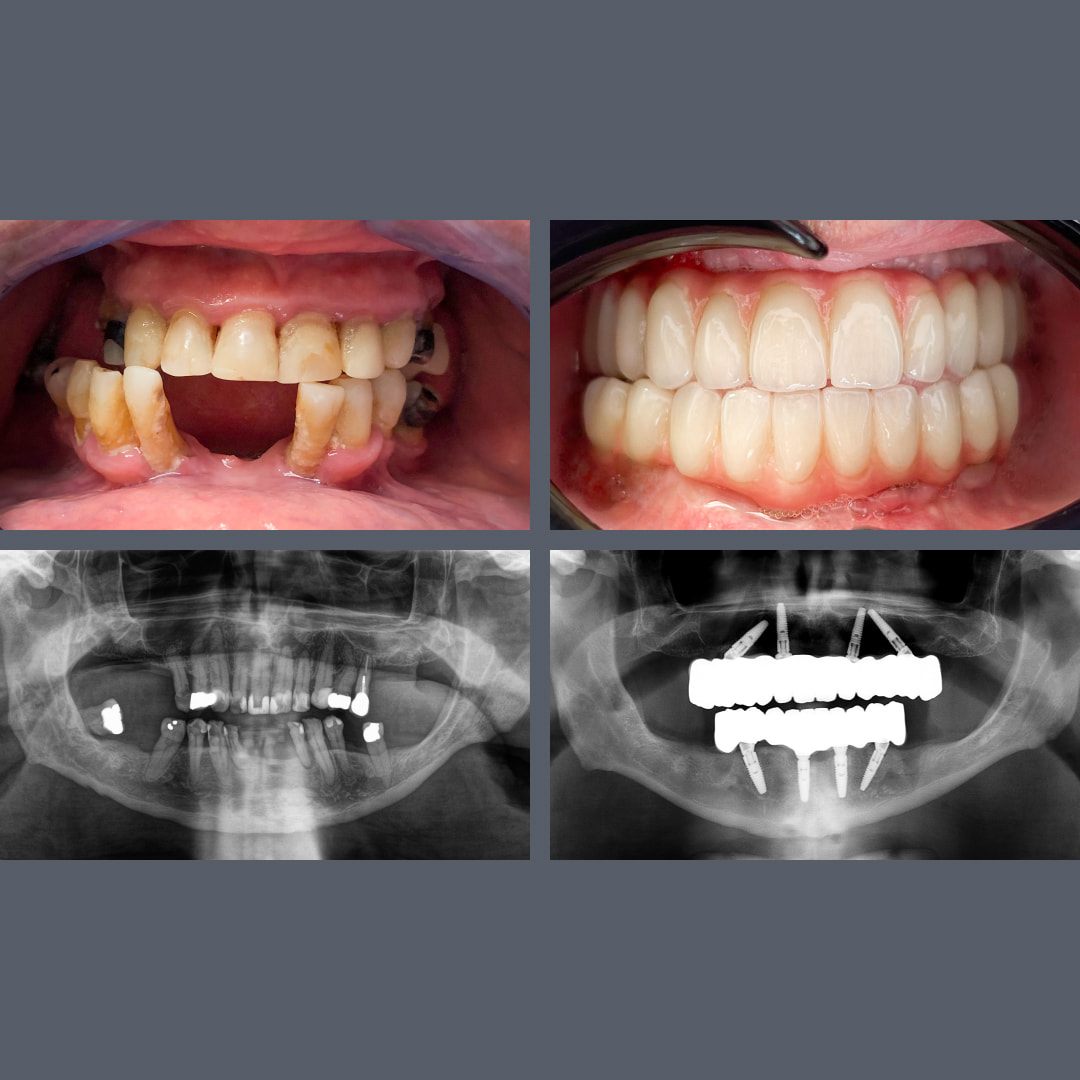

Fra gammel bro til fast og æstetisk løsning: All-on-4® i overkæben på 5 måneder